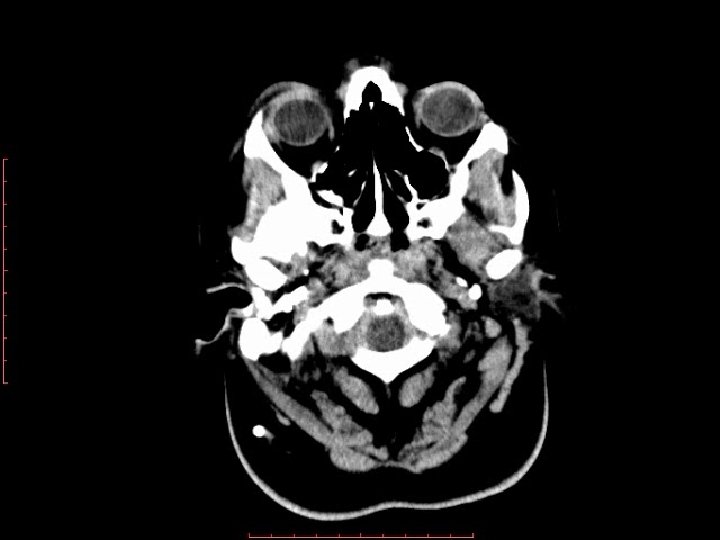

KT əlamətlər � Geniş arxa kəllə çuxuru � Müxtəlif ölçülərdə kista � Sagital lambdayabənzər tikişin inversiyası. � Mega sisterna magna daxil olmaqla butun DW tiplərində ənsə sümüyünün daxili səthinin formasının dəyişilməsi

Differensial diaqnostika Ø • • Araxnoid kista Bəzi ədəbiyyatlarda DWS-na aid edilir IV mədəcik kompressiya olunub, yeri dəyişilir ancaq normal konfiqurasiyalı AK içərisindən beyincik orağı, incə venalar keçmir AK-lərin daxili səthi araxnoid hüceyrələr /kollagen ilə örtülüdür

T 1 sagital kəsikdə beyincik yarımkürələrinə , soxulcan , IV mədəciyə və beyin kötüyünə təzyiq edən böyük ölçülü araxnoid kista